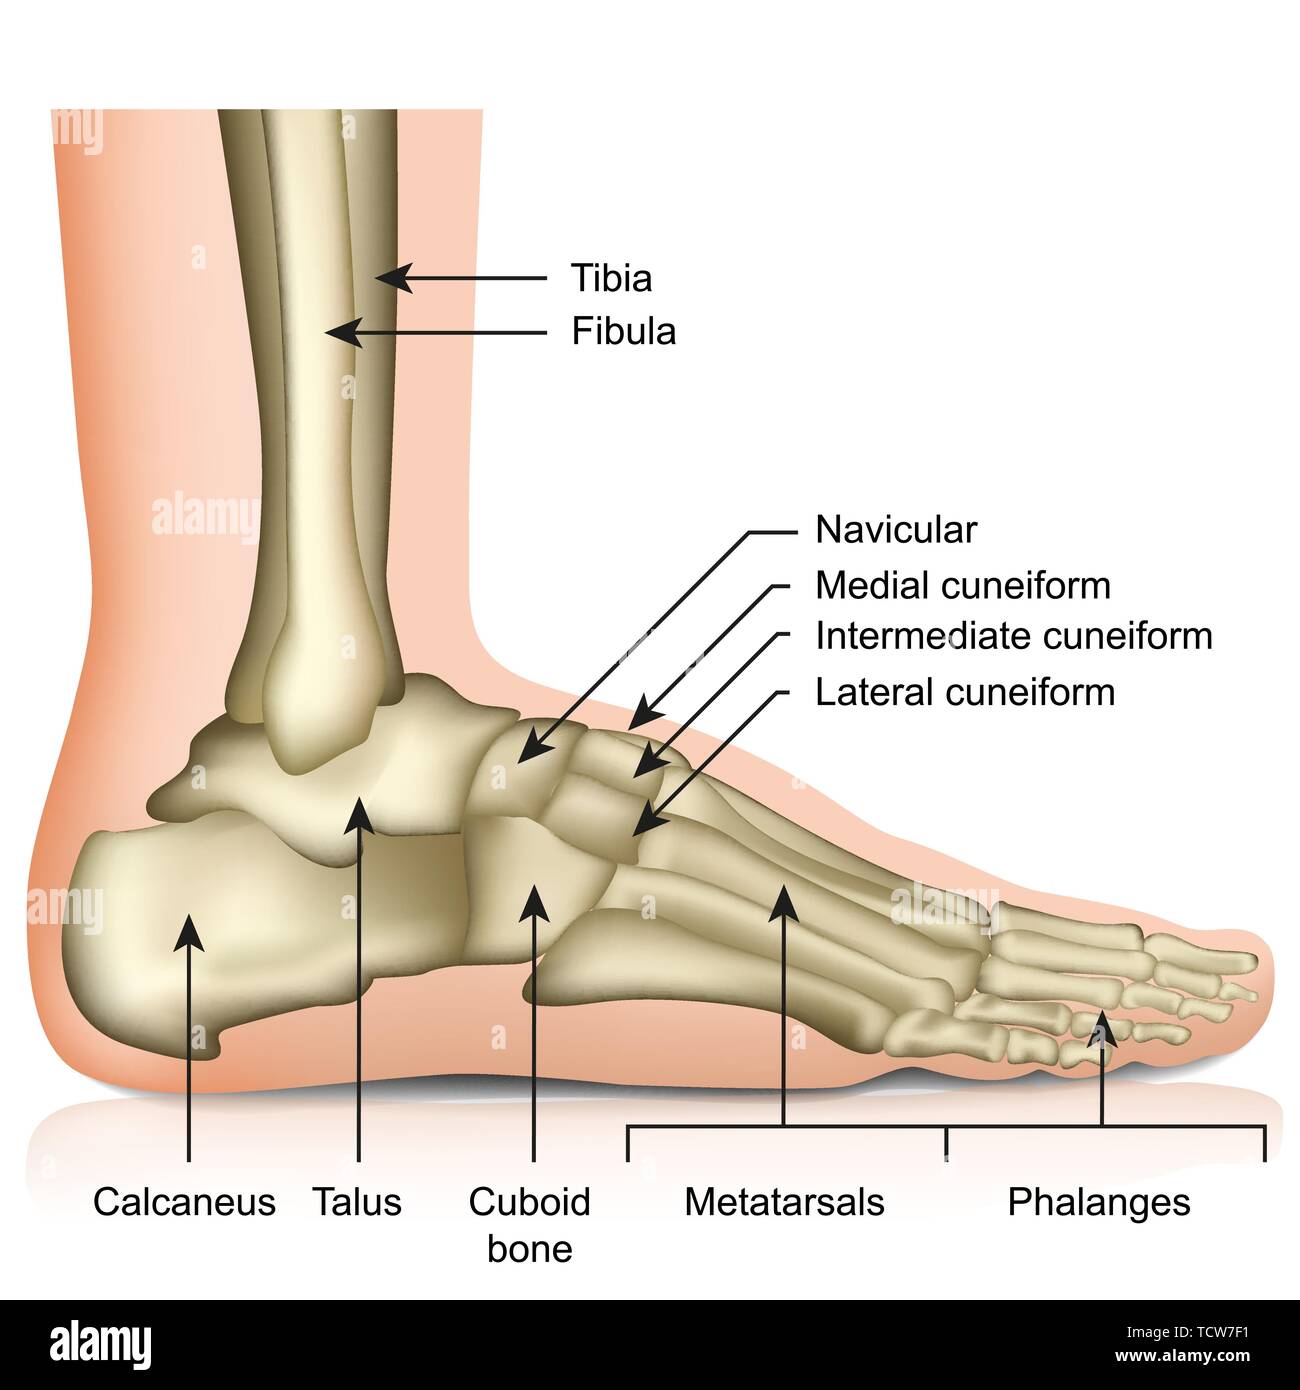

RF2DHMD0H–OS du pied. Anatomie humaine. Le schéma montre l'emplacement et le nom de tous les os du pied.

RFTCW7F1–Os du pied et de la cheville d'illustration vectorielle médical isolé sur fond blanc eps 10 Infographie

RF2R3WKY1–Illustration médicale des principales parties des os du pied en vue latérale, avec annotations.